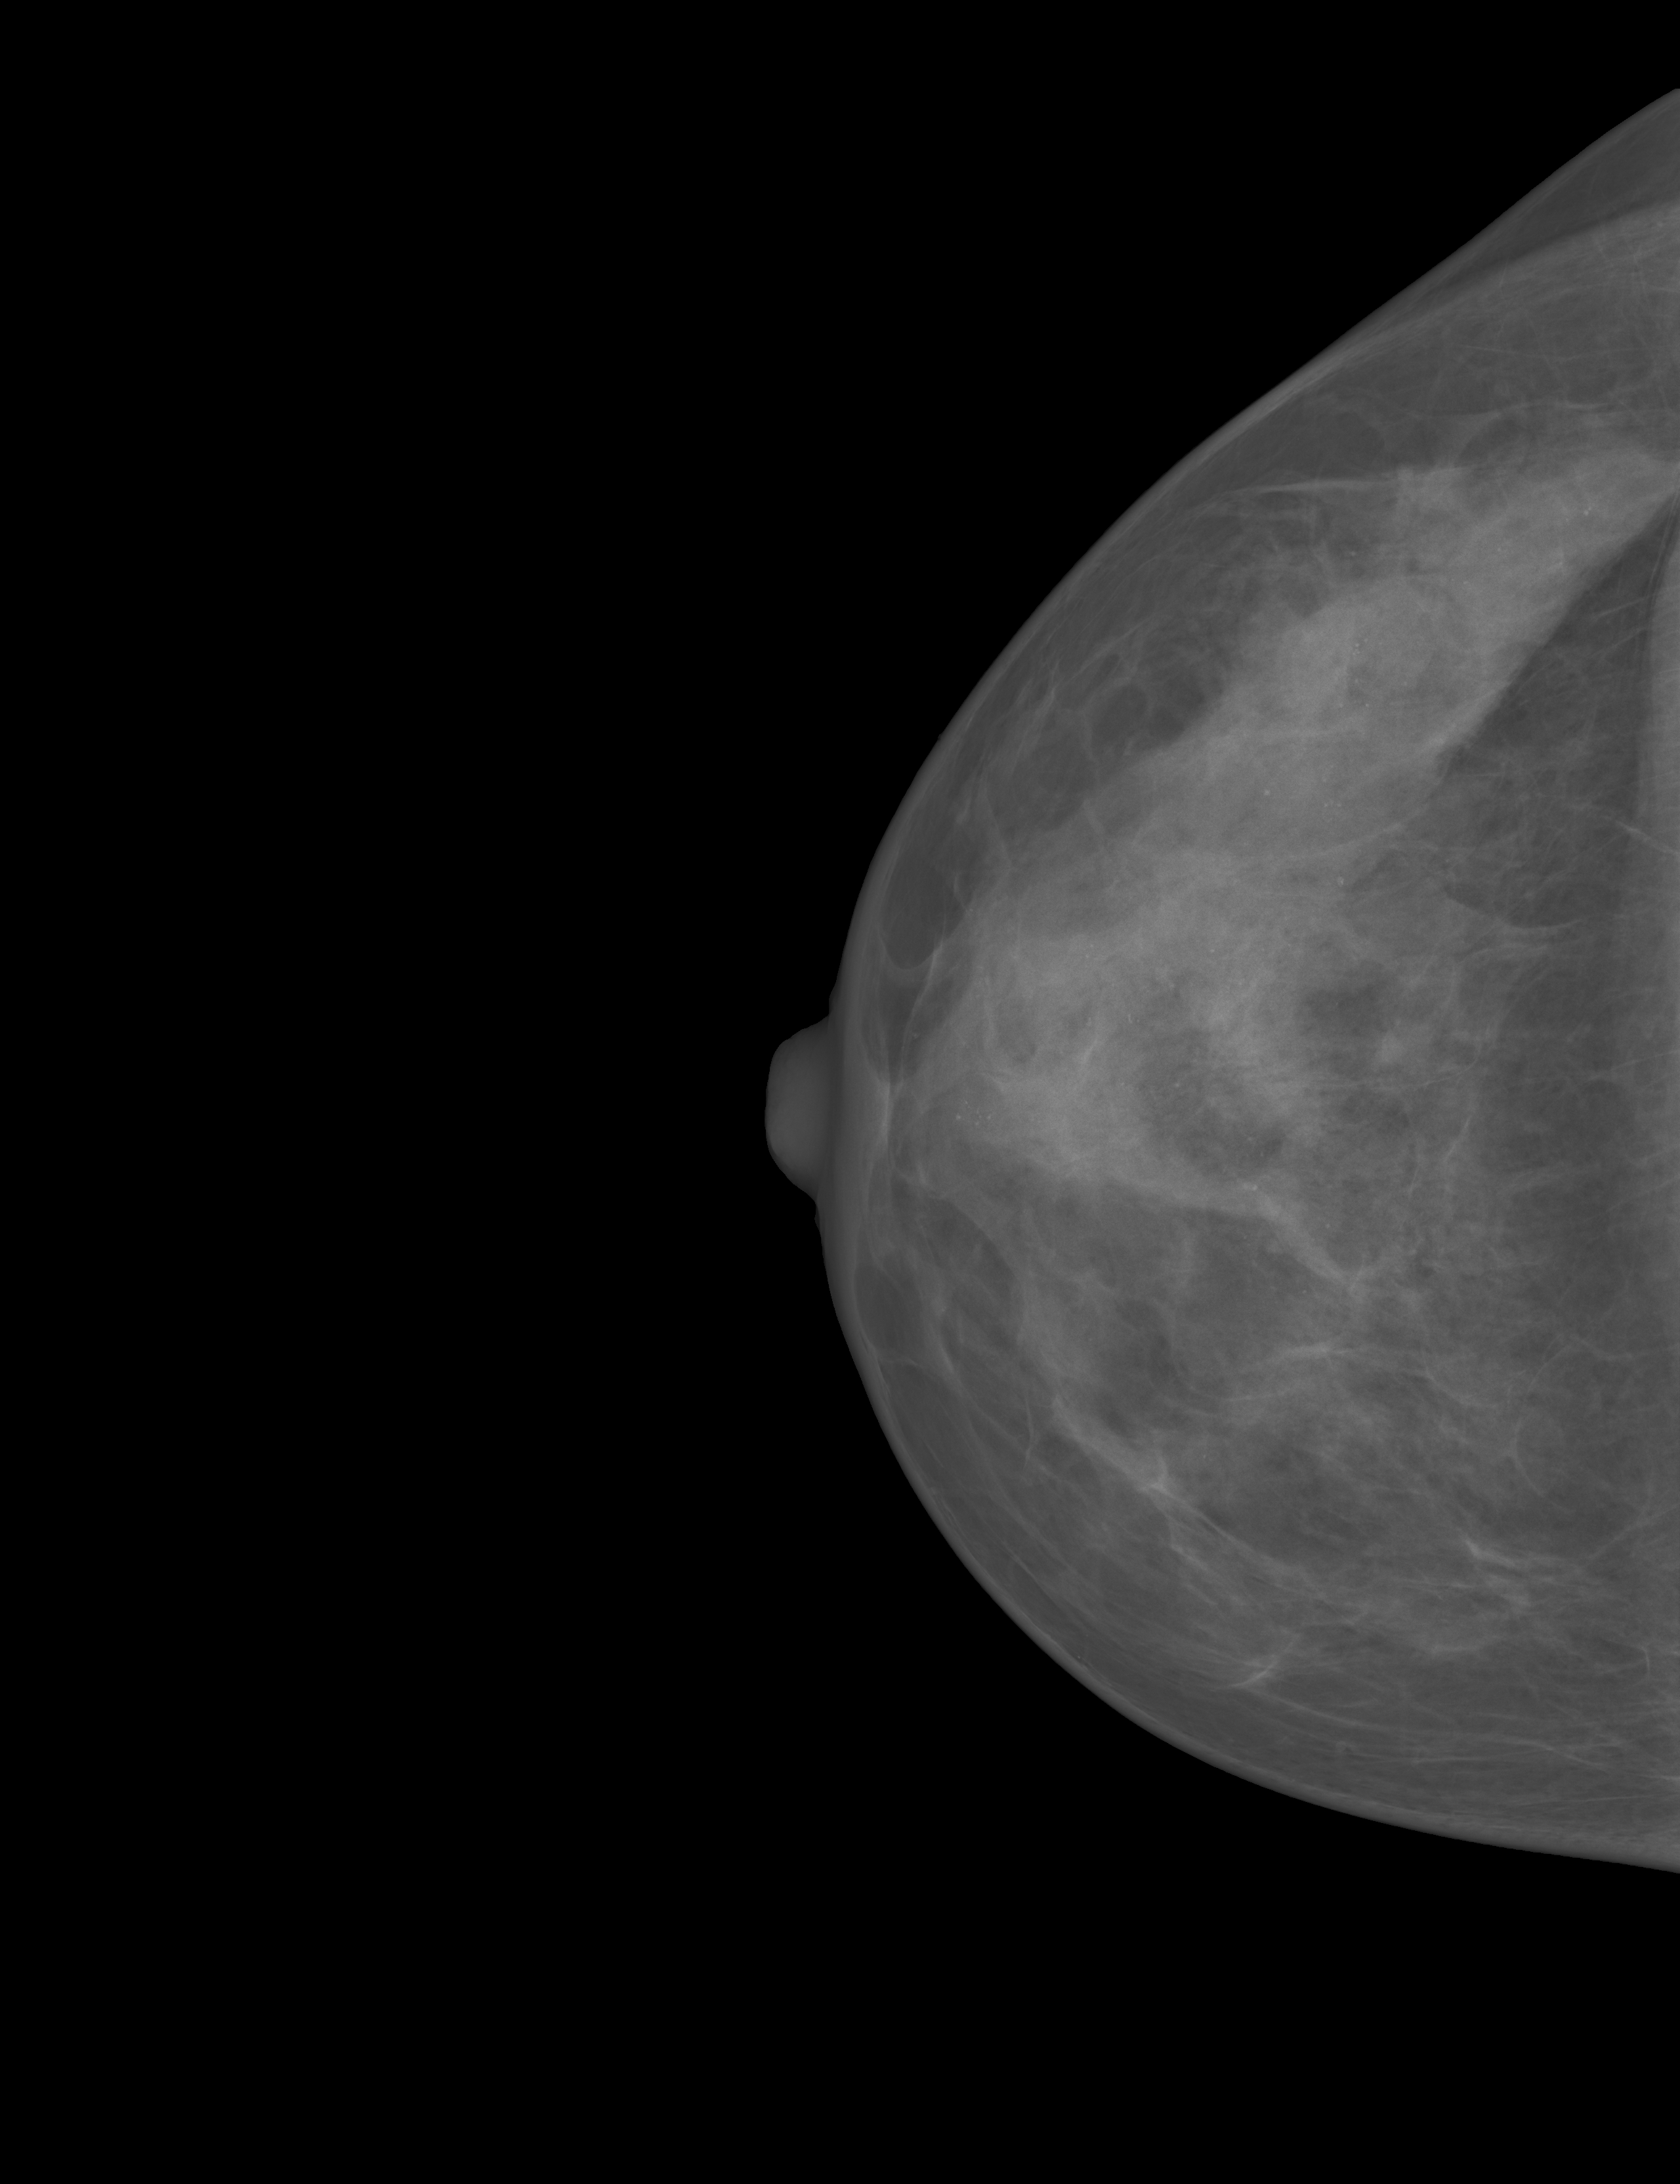

In this study, we evaluated our methods on the public available dataset, INbreast dataset[21], which contains 115 cases (410 images). Among the 115 cases, 90 cases are from women with both breasts affected (4 images per case) and 25 cases are from mastectomy patients (2 images per case). Two views for each breast were recorded, a craniocaudal (CC) view, which is a top to bottom view, and a mediolateral oblique (MLO) view, which is a side view. The dataset provides a breast density assessment of each mammograph with the corresponding labels of BI-RADS categories, which makes it suitable for our study. The mammographs were acquired on x-ray films and saved by the standard Digital Imaging and Communications in Medical (DICOM) format. The image matrix has either 3328×4084332840843328\times 4084 or 2560×3328256033282560\times 3328 pixels. Among the 409 images(1 missing the label), 136 are classified as BI-RADS I, 146 as BI-RADS II, 99 as BI-RADS III and 28 as class BI-RADS IV (example images of four categories are shown in Fig 1).

Figure 1: Example of mammographs of the different BI-RADS categories. (a) BI-RADS I, (b) BI-RADS II, (c) BI-RADS III, and (d) BI-RADS IV.